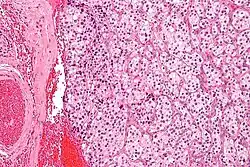

Makroskopisch sind sie vorwiegend rund-ovale, rotbraune bekapselte Gebilde, die gelegentlich den Knochen infiltrieren. Histopathologisch bestehen sie aus Zellballen, die von einem feinen kapillaren Netzwerk umgeben sind. Immunhistochemisch enthalten die Zellen Chromogranin A und Synaptophysin. Um die Zellballen liegen teilweise sogenannte Sustentakularzellen, die S100-Protein enthalten.

- Pathohistologie auf Pathorama